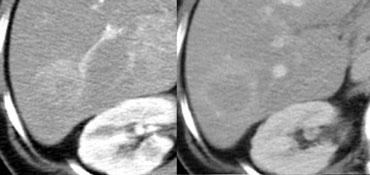

Ung thư biểu mô tế bào gan kích thước nhỏ trên nền gan xơ: không quan sát thấy trên CT không tiêm thuốc (trái), hiện rõ trong thì động mạch (giữa) và không quan sát thấy trong thì tĩnh mạch cửa (phải)

Khả năng phát hiện một tổn thương gan phụ thuộc vào sự chênh lệch tỷ trọng giữa tổn thương và nhu mô gan bình thường.

Trên CT không tiêm thuốc cản quang (NECT), các khối u gan thường không quan sát được do độ tương phản vốn có giữa mô u và nhu mô gan xung quanh quá thấp.

Do đó, cần tiêm thuốc cản quang tĩnh mạch để tăng khả năng hiển thị của các tổn thương.

Tuy nhiên, tất cả các khối u gan đều nhận 100% nguồn cung cấp máu từ động mạch gan, vì vậy khi ngấm thuốc sẽ xảy ra trong thì động mạch.

Sự khác biệt về nguồn cung cấp máu này dẫn đến các kiểu ngấm thuốc khác nhau giữa khối u gan và nhu mô gan bình thường trong các thì tiêm thuốc cản quang khác nhau (hình).